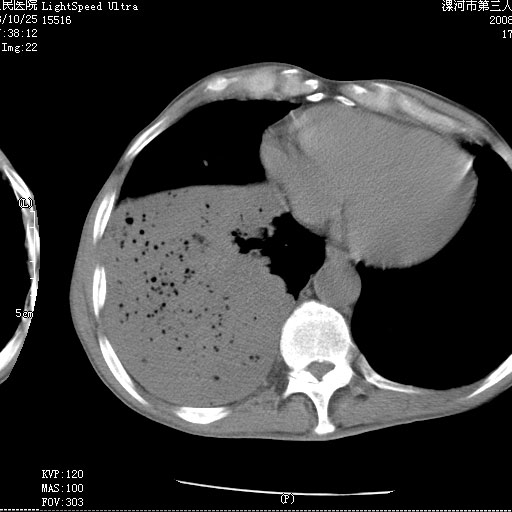

m 老年 发烧、呼吸困难,慢支、肺气肿多年;记的那次是下午大概17:38做的,晚上窒息死亡。

上面的层面就慢性支气管炎肺气肿、肺大泡,别的没有什么、也就不传了。

当时我怀疑:1、阻塞性肺不张早期 2、肺脓肿早期,望老师们发表意见

应该是脓胸的表现,右下肺气管阻塞考虑为痰栓.

你怀疑的有道理,慢支、肺气肿、肺打泡是有了,右下肺的病变有待商议;

首先考虑右下肺炎症并不张,不除外早期肺泡癌改变

病灶边缘清---多个含气小腔---近端未见通畅气管影-----支持-----慢性肺脓肿继发阻塞性肺不张

阻塞性肺不张原因-----脓液未排出

1、右侧脓胸;2、copd;

3、细支气管肺泡癌可以排除,病变以斜裂为界,呈大片状高密度影,内可见多发小气泡,表明有产气杆菌感染所致,内无明显的支气管“枯树枝征”表现,再结合其临床改变(细支气管肺泡癌临表表现重、影像表现轻)所以不符合细支气管肺泡癌(炎症型)的改变。

病变按肺叶分布,病变内可见多个小空腔影,未见充气支气管影,中间段支气管管腔肺窗示密度欠均匀,下肺支气管分叉处基底段支气管隐约可见,未见明显狭窄,中叶支气管通畅,

考虑:阻塞性肺炎伴小脓肿形成可能性大。(痰栓可能性大)

右下肺实变,内有弥漫分面小气泡而无支气管征,叶间裂前移,呈臌大之形,而无收缩之状,兼纵隔稍左行移,故。不支持不张,倒支持大叶肺叶,如楼上所说,小气泡不象残留之肺,不可以考虑产气菌感染吗。

阻塞性肺炎,肺脓肿形成。依据,右下支气管不通,大片实变形内可见小气泡。不支持肺不张。